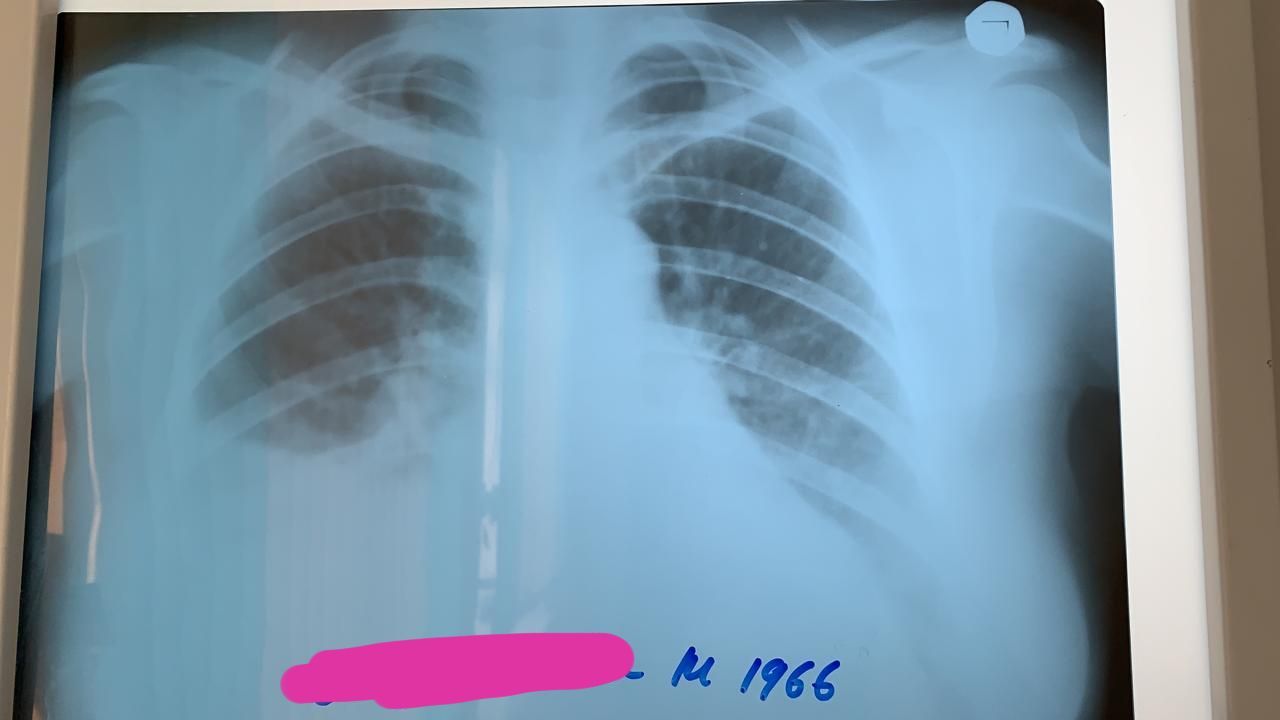

Это после.

Ок. Обе снимки сегодня снято. 1до 2 ой после пункции

Ок. Динамика положительная. Для уточнения положения жидкости правый бок